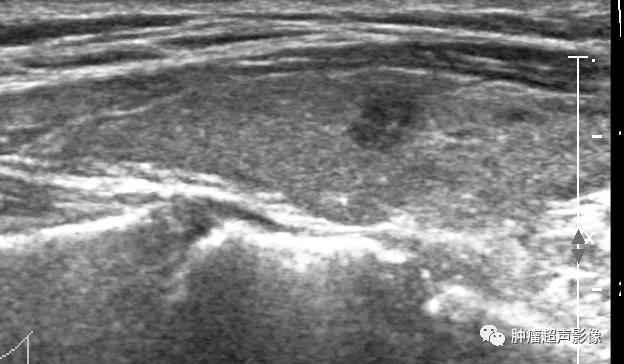

上图:甲状腺结节呈低回声,边缘不光整,纵横比大于1,内见点状强回声,可分到5类,内部无血流,

回顾以前检查可发现同一位置有一囊实性结节(下图),从而确诊皱缩结节,避免穿刺及手术。